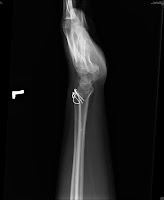

Tension band wiring for ulnar styloid process fracture (3 yeas F/U)

Post-OP

6 weeks F/U

1 year F/U

3.5 years F/U